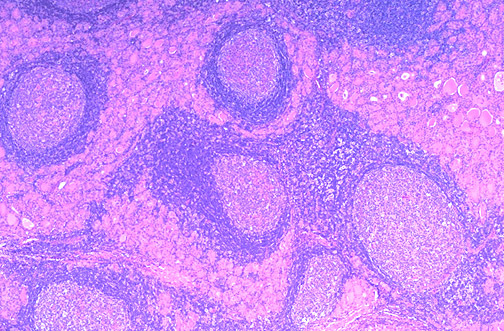

This low power microscopic view of thyroid gland shows an early stage of Hashimoto thyroiditis with prominent lymphoid follicles containing large, active germinal centers. In this autoimmune disease, antithyroglobulin and antimicrosomal (thyroid peroxidase) autoantibodies can often be detected in serum. Other autoimmune diseases such as Addison disease or pernicious anemia may also be present. Both thyroid growth immunoglobulins (TGI) and thyroid stimulating immunoglobulins (TSI) are present, though blocking antibodies to TSI mitigate their effect so that hyperthyroidism is usually not the most prominent features.